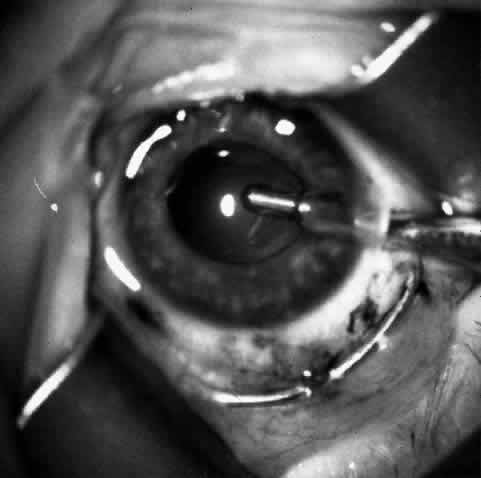

At this point, if intraocular surgery, that is, cataract extraction, pupilloplasty, or membranectomy, is to be done, it is performed through a limbal incision with a vitreous cutting instrument such as the Microvit or Ocutome (Fig. 8). The limbal incision may be closed with 8-0 polyglactin 910 (Vicryl) sutures. After the intraocular procedure is completed and before the epikeratophakia procedure is resumed, it is important to return the eye to normal pressure by injecting balanced salt solution. I prefer to accomplish this with a 30-gauge sharp paracentesis injection through clear cornea.

Fig. 8. After trephination, intraocular surgery may be carried out through a limbal approach if required. Note that the Flieringa ring shown is no longer routinely used.